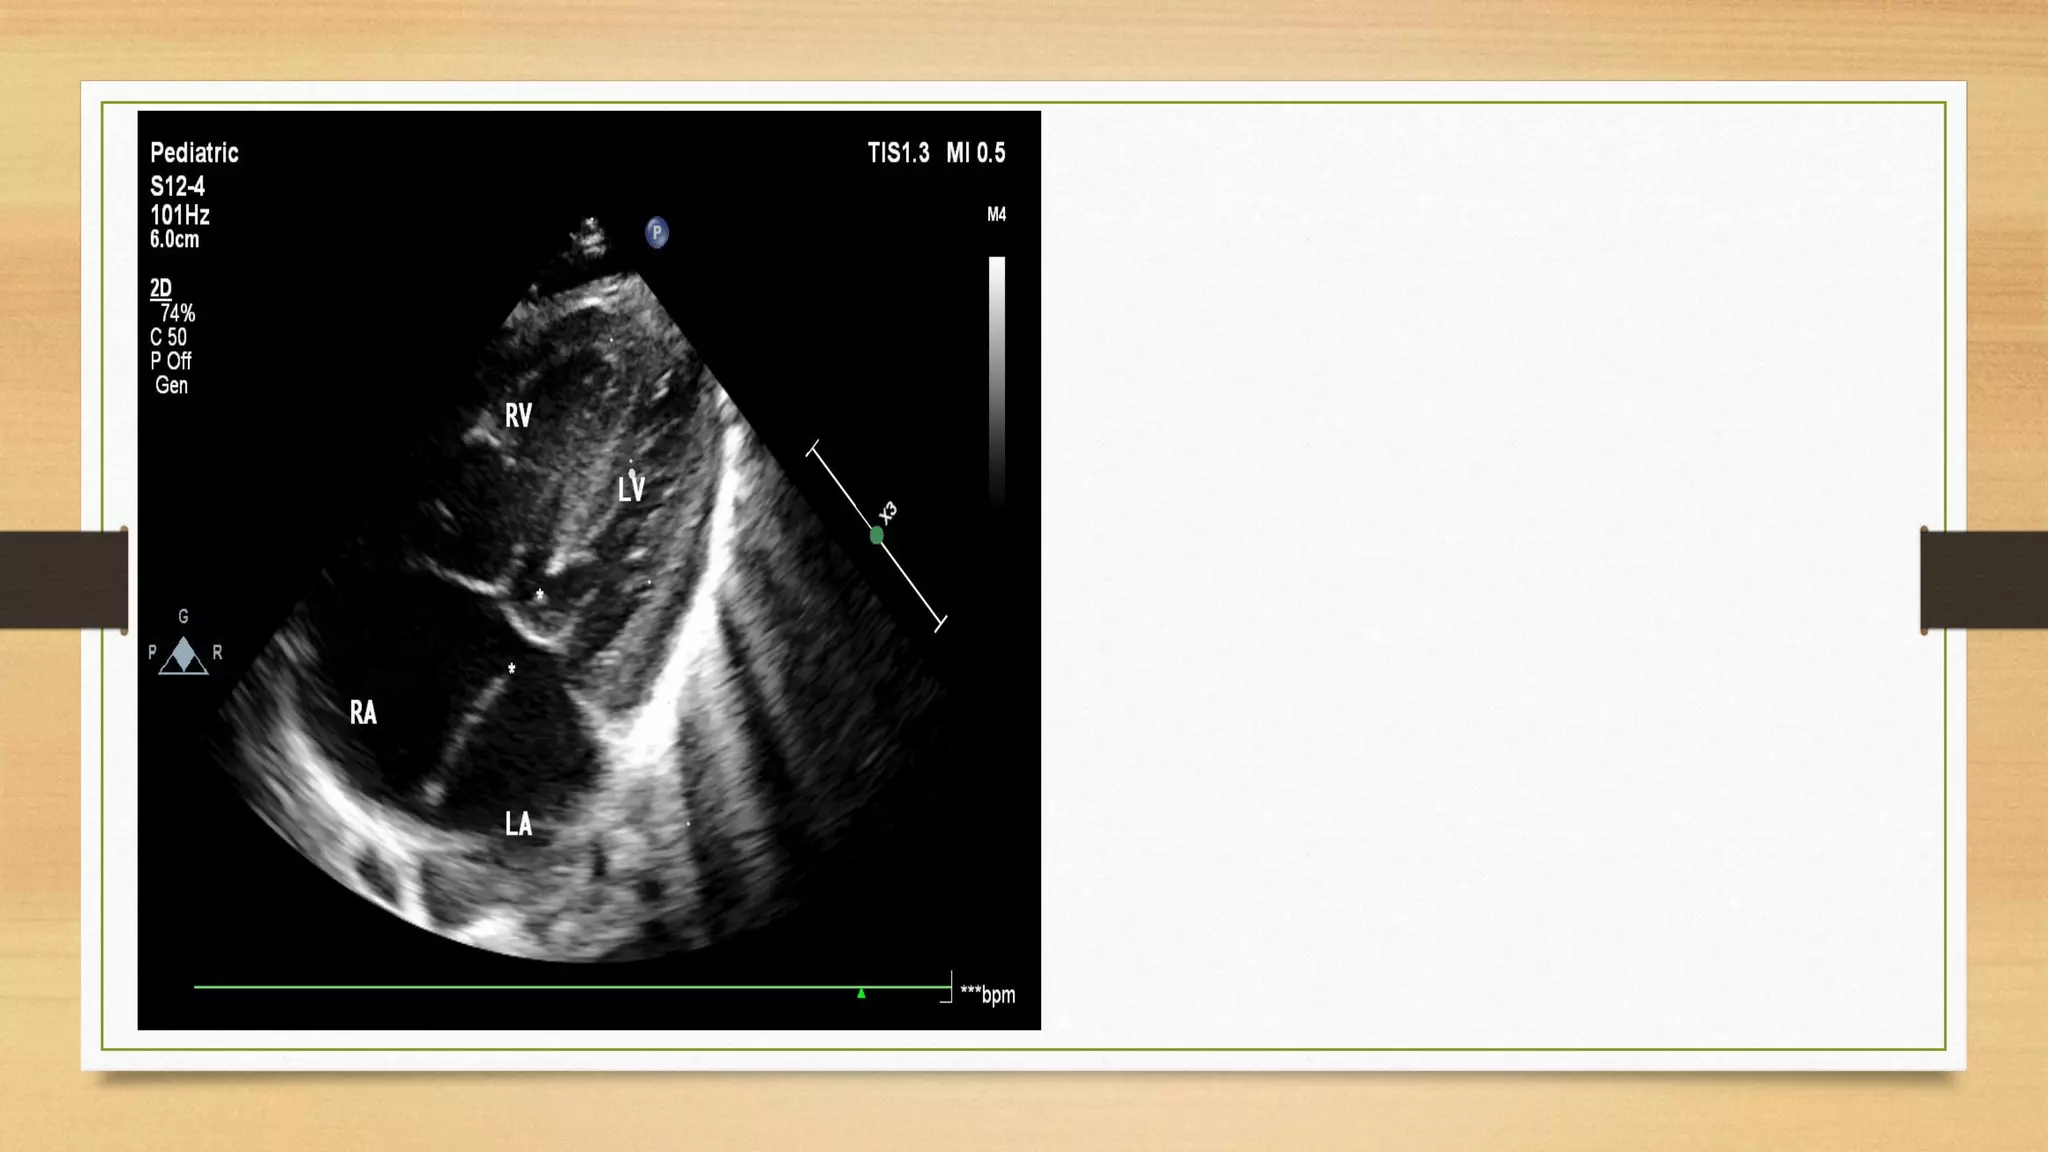

Level of Atrioventricular Valve Insertion :

In normal hearts, the tricuspid valve inserts onto the ventricular septum more apically than

the mitral valve. With this “offset” in the level of insertion, a portion of septum, called the

AV septum, separates the right atrium (RA) and the left ventricle. In AVSDs, both right

and left AV valve components insert at the same level, and this is best appreciated from an

apical four-chamber view. Apical four-chamber imaging demonstrates the crux of the

heart, which has been referred to as the most reliable and consistent intracardiac

landmark.

Atiro-ventricular valve should be seen in apical 4 chamber view ( may not be seen in basal and lateral

4 C view) to look for loss of offset, both valve At one level like bird wing, seagull sign.

Right atrial length is 40% of right ventricular length, and ratio is 40%, This ratio is increases and RA

may be equal to right ventricle length. Color Doppler depict central jet of regurgitation.